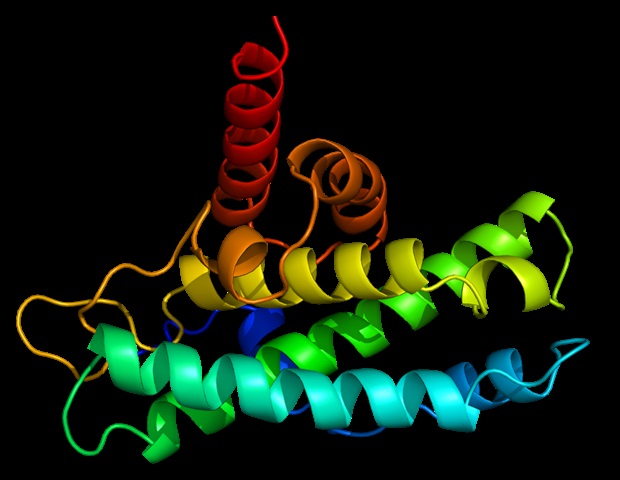

מחקר חדש מאוניברסיטת ויסקונסין-מדיסון מגלה שחוסר תפקוד בחלבון החיוני לשמירה על יציבות בכרומוזומים שלנו עשוי להיות אחראי למחלות קשות –

מחקר בראשות חוקרי מרכז הסרטן המקיף של UCLA Health Jonsson חושף כיצד מלנומה, הצורה הקטלנית ביותר של סרטן העור, מתפתחת